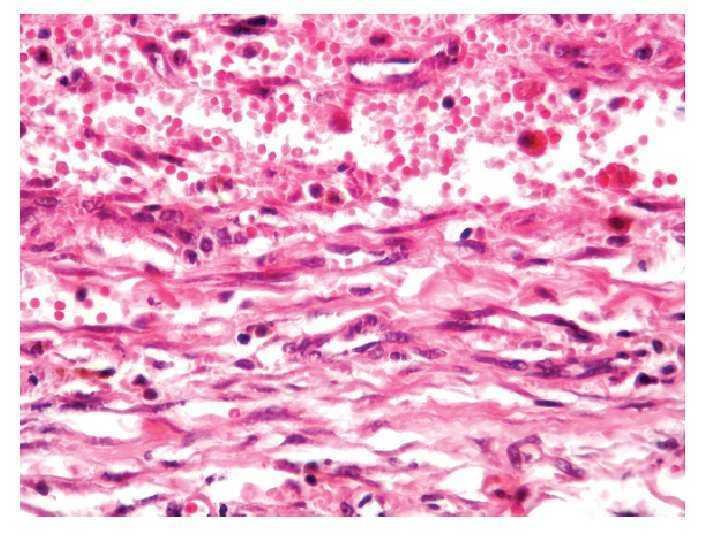

Imagen 4. Vista microscópica.

Se realizó nefrectomía radical derecha con hallazgos de hematoma retroperitoneal, sin sangrado activo y con presencia de tumor renal de 7 cm. El diagnóstico histopatológico fue de angiomiolipoma renal (AR) (Imagénes 1 y 2).

Patológicamente existen dos tipos de angiomiolipomas: el clásico contiene músculo liso, vascular, graso y raramente infiltración perirenal, el segundo tipo contiene un cuarto componente de células epitelioides perivasculares, haciéndolo más agresivo que el angiomiolipoma tradicional, de aquí la variación invasiva que constituye una variación maligna. Los marcadores inmunológicos principalmente HMB-45 que marca células perivasculares de tipo epitelioide. Otros marcadores son la actina y CD-68.7 El tratamiento está indicado en la sospecha de malignidad, hemorragia espontánea, sintomatología intensa y riesgo de ruptura. Con el objetivo central de preservar la función renal. Las indicaciones de tratamiento aún no están bien definidas, se basan en que tumores mayores a 4 cm pueden ser tratados con procedimientos quirúrgicos debido a las complicaciones posibles. Con tratamientos no invasivos en tumores asintomáticos menores a este tamaño.4